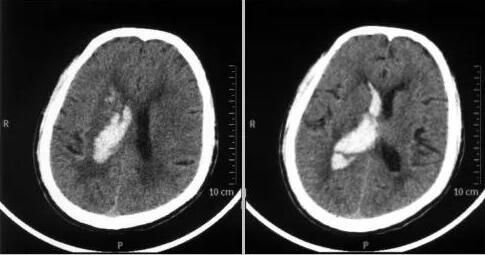

送到当地医院已经是数个小时之后的事情,急诊进行头颅CT检查,发现右侧基底节区脑出血并破入脑室。急诊进行降颅压等对症处理之后,随后几天即按脑出血进行保守治疗,但是情况并没有明显好转。在当地医生的建议下,家属将张老先生转运到广东三九脑科医院做进一步治疗。